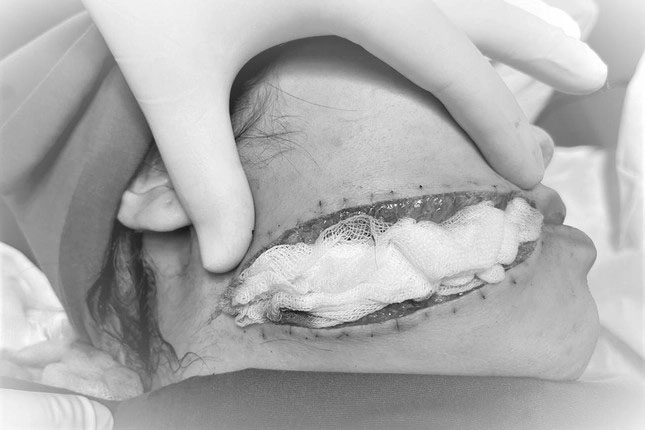

Vết thương dài 12cm kéo dài từ môi đến sát vùng cổ gáy của bệnh nhân

TS.BS Tú Dung cho biết: “Sau khi mở và vệ sinh vết thương, chúng tôi phát hiện bệnh nhân bị đứt cơ mặt vùng môi, cơ vòng miệng và một phần cơ vòng má. Sau khi nối các cơ bị đứt, ê kíp đã khâu thẩm mỹ 4 lớp cho bệnh nhân. Nếu không được phẫu thuật lại, các cơ vùng mặt bị đứt sẽ khiến bệnh nhân bị méo miệng, khuôn mặt sẽ mất khả năng biểu cảm. Bên cạnh đó, bệnh nhân sẽ đối mặt với vết thương để lại sẹo lớn trên mặt gây ảnh hưởng đến cả thể xác và tinh thần suốt phần đời còn lại”.

Dự kiến, sau khi vết thương bình phục, cô gái trẻ sẽ được bác sĩ chiếu laser và hỗ trợ điều trị để làm mờ sẹo, giữ lại thẩm mỹ cho gương mặt của bệnh nhân.